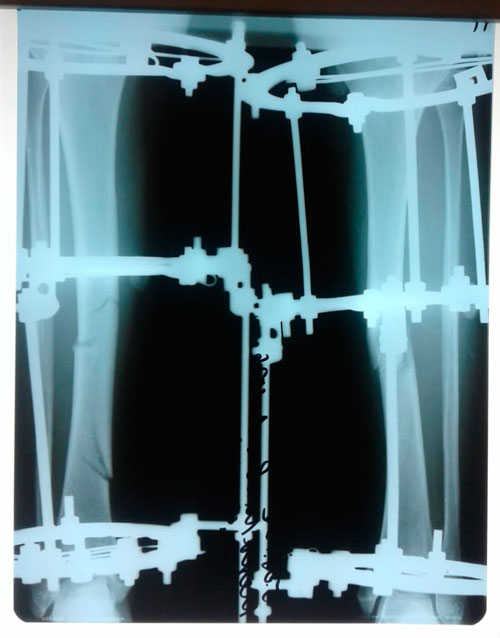

Исходник -43 года.

Дата операции - 18.07.2019г.

Диагноз: нетипичная варусная деформация голеней, на границе нижней и средней/3

Исправление по методике доктора Онипко Н.Н.